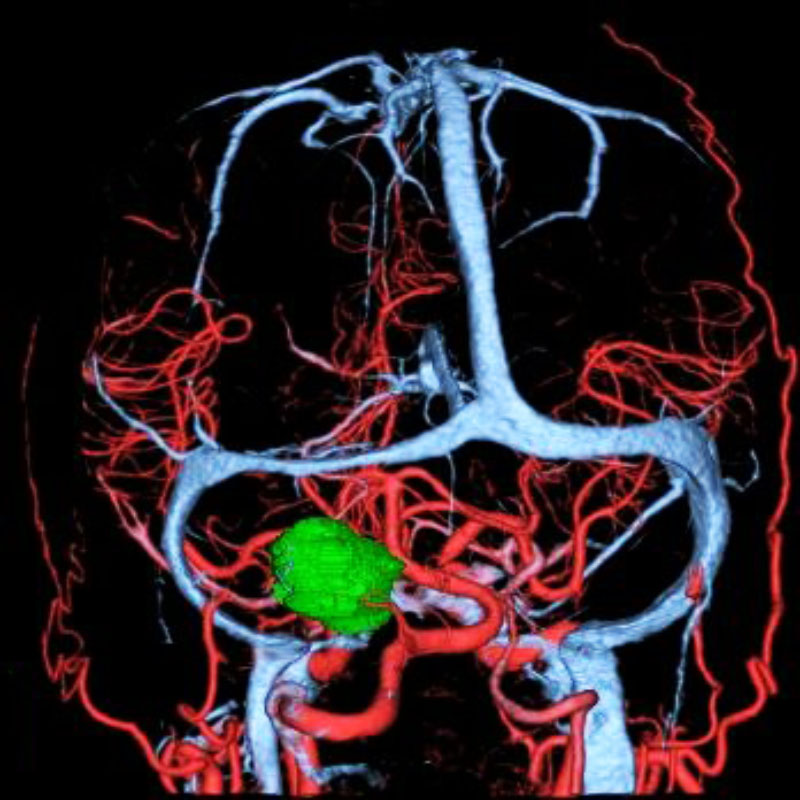

脳動静脈奇形

血管塞栓術

松田/濵田/元永